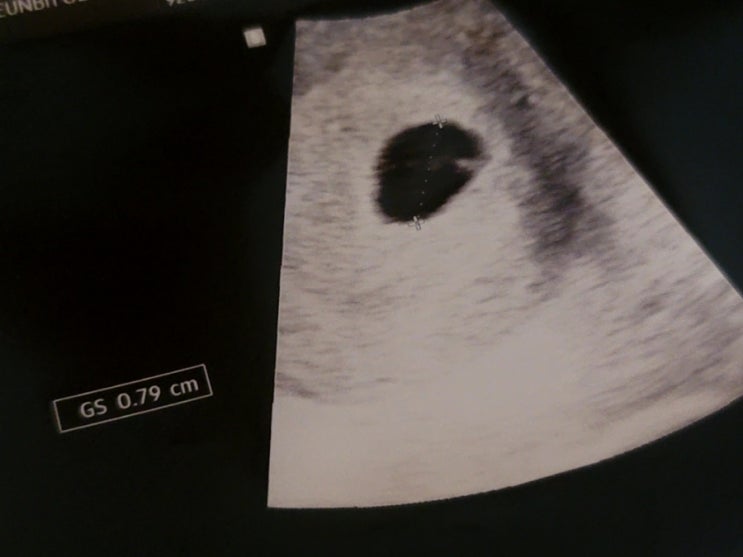

[임신 이야기] 임신6주차/3차 병원 진료의뢰/자궁각임신/찌그러진 아기집/임신무증상/태아느린발달

본 포스팅은 임신 일기입니다. 2022.12.24 어제는 많은 일들이 있었다. 금요일. 임신 전에 12월 근무표가 ...